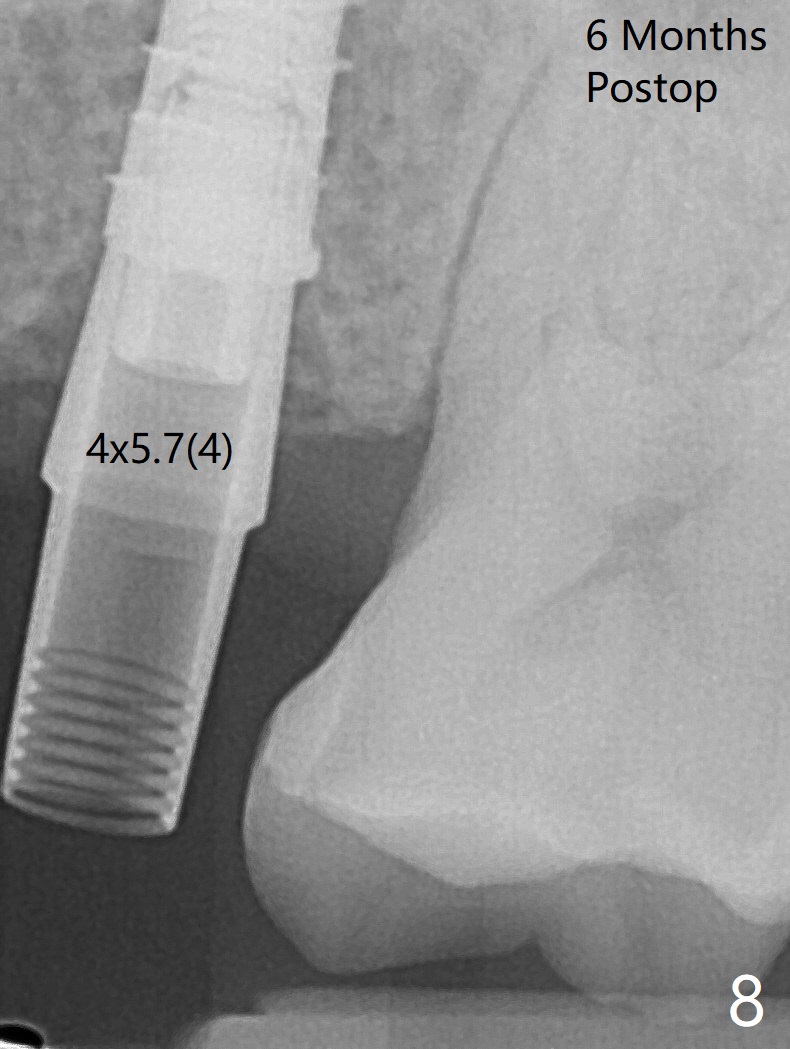

When a 4x11 mm FC is placed to the depth at #13, the palatal crestal bone is indistinct on probing. The implant is then placed ~ 1 mm deeper. To avoid contact between the future abutments and the mesiobucco-distal crest, a 5.5 mm profile drill is used. It appears that a 5x4 mm healing abutment has clearance from the crest (Fig.1,2 C). Immediate postop CT 3 D palatal view shows slight possible implant (Fig.3 I) thread exposure disto-palatal. To avoid this situation, the implant should have been designed more buccal (Fig.4 coronal section) because of the preexisting palatal defect (Fig.5,6) with low bone density palatocoronally (Fig.7). CT should have been taken prior to extraction. PRF or GEM21S should have been used. The patient will return for restoration (probably progressive loading) 3 months postop. In fact a pair abutment is placed 6 months postop (due to coronavirus, Fig.8). There is crestal bone palatal to the implant 6.5 months postop (Fig.9).